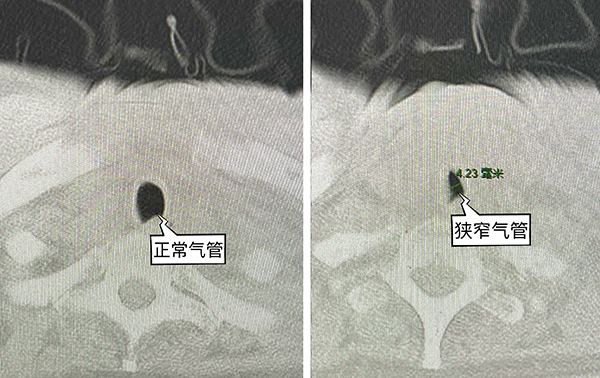

對于身經百戰的手術醫生及麻醉醫生來說,這本身是一臺常規的手術。然而火眼金睛的麻醉醫生在術前的例行訪視時發現了一個問題:患者肺部CT顯示有一段氣管明顯狹窄,內徑僅4mm左右,小于適合成人的各型號氣管導管內徑,存在明顯的氣管插管困難。這就給麻醉帶來了不小的挑戰,如果麻醉誘導后插管失敗,患者的處境將會十分危險。